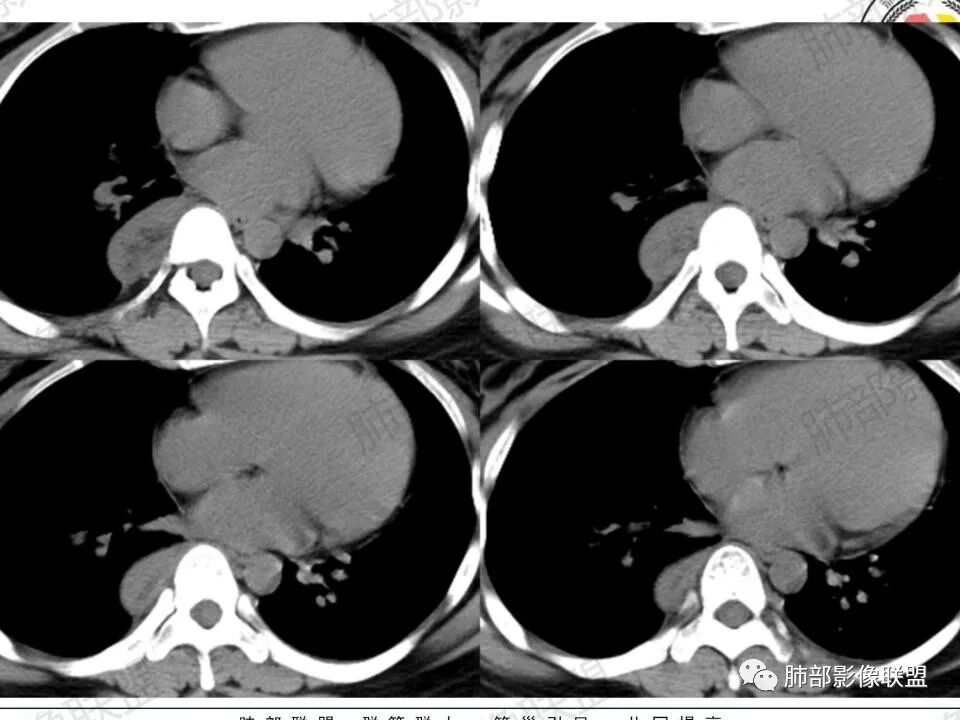

2.右后纵隔脊柱旁上下方向贴伏块影,“肾”形外观,边界清晰,密度不均,中央区域见脂肪密度影引向椎体前方,未见液性密度管腔影及钙化。

3.块影血供动脉来自肋间动脉,且由内后方侧入,其与下腔静脉之间未见回流通道。血管未见破坏,相邻组织未见侵入。

4.块影未延伸至椎管内,未见椎间孔扩大或骨质吸收破坏。

1.肿块未横向经椎间孔延入椎管,或形成所谓“哑铃状”外观等,没有显示出沿脊神经根生长特征。长轴顺脊柱贴行恰好与交感神经路径相一致。

2.肿块含脂肪等成分,与交感神经路径相一致,渐进性轻度强化(可能含有粘液成分)等,以节细胞神经瘤最可能!尽管未显示“习惯性”的钙化。

瘤体体积常较大,大部分有完整包膜,边界清楚,可沿周围组织间隙嵌入性生长,由于肿瘤质地较软,使得肿瘤可呈多种形态,其易沿着周围组织间隙生长、包饶,但不挤压周围器官或组织,邻近血管被包绕或穿行,呈嵌入式或铸型生长方式,这是后纵隔神经节细胞瘤的特征性表现;

还有另外一种形态学特征,瘤体的上下径线常大于其他径线,这可能是神经节细胞瘤起源于交感神经节,而交感神经节纵向分布于近脊柱中线两旁及前方,导致了后纵隔神经节细胞瘤纵向生长的范围大于向其他方向生长的范围,其上下可跨越多个椎体。但后纵隔神经节细胞瘤体积较小时,则常呈圆形、椭圆形、哑铃形等形态,紧贴后纵隔或后胸壁。